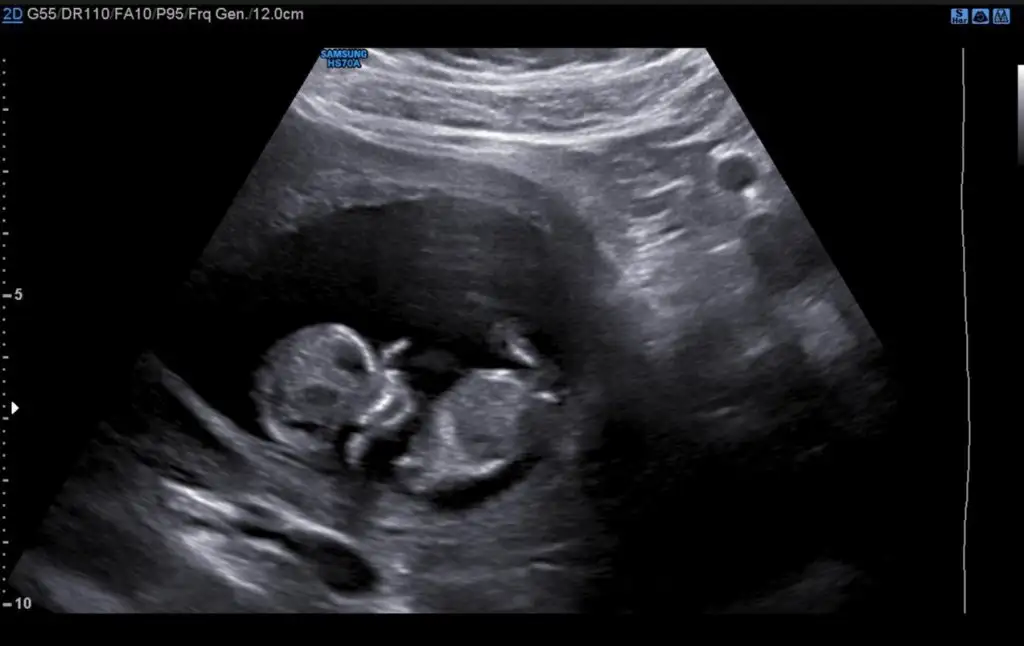

Dun gondermistim, bugun donus yapmis.Ben gönderdim 9+4 deki ultrasonu bana %80 kız dedi bakalım bilecek mi